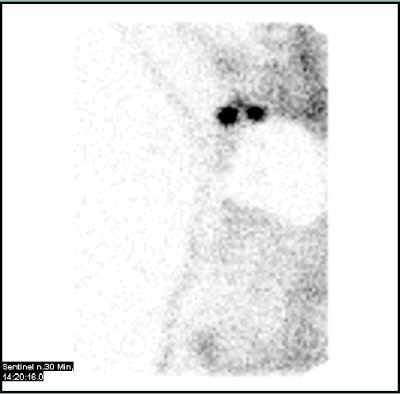

Die Sentinellymphknoten-Szintigraphie betrifft den oder die Wächterlymphknoten, also den oder die Lymphknoten, die einem Tumor unmittelbar nachgeschaltet sind.

Nach Darstellung und Markierung des oder der Wächterlymphknoten werden diese chirurgisch entfernt und feingeweblich untersucht. Abhängig von einem evtl. Tumorbefall des Wächterlymphknotens ergeben sich dann der Umfang der Tumoroperation und ggf. auch die Notwendigkeit einer zusätzlichen Bestrahlung und/oder Chemotherapie.

Die Sentinellymphknoten-Szintigraphie gehört heute zum Behandlungsstandard vieler Tumorerkrankungen, insbesondere auch bei Brust- und Prostata-Krebs.